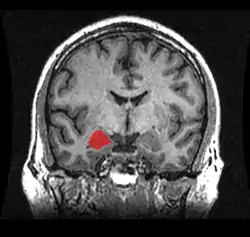

El cuerpo amigdalino, complejo amigdalino o amígdala cerebral es un conjunto de núcleos de neuronas localizadas en la profundidad de los lóbulos temporales de los vertebrados complejos, incluidos los humanos.[1] La amígdala forma parte del sistema límbico, y su papel principal es el procesamiento y almacenamiento de reacciones emocionales.[2][3]

Las regiones descritas como «amígdala» en realidad abarcan una serie de núcleos con distintos atributos funcionales llamada complejo amigdalino. Entre esos núcleos se encuentra el grupo basolateral, el núcleo centromedial y el núcleo cortical. El grupo basolateral se puede dividir a su vez en el núcleo lateral, el basal y los núcleos basales accesorios.[2][4]

Con los avances en las técnicas de neuroimagen, como por ejemplo la tomografía por emisión de positrones o la resonancia magnética funcional, los neurocientíficos han hecho grandes averiguaciones en torno a la amígdala en el cerebro humano. Datos consensuados demuestran que la amígdala tiene un papel importante en los estados mentales, y que está relacionada con muchos trastornos psicológicos. En 2006, investigadores observaron una hiperactividad en la amígdala cuando se mostraba a los pacientes caras amenazantes o se veían implicados en situaciones terroríficas. Pacientes con una fobia social más severa correlacionaban con una mayor activación de la amígdala.[17] De forma parecida, pacientes depresivos mostraron una hiperactividad de la amígdala izquierda cuando interpretaban emociones para todo tipo de caras, y especialmente con caras amenazantes. Esta hiperactividad se normalizó cuando a los pacientes se les prescribió un tratamiento con antidepresivos.[18] Por el contrario, se ha observado que la amígdala actúa de forma diferente en pacientes bipolares. Un estudio del 2003 halló que tanto pacientes adultos como adolescentes con trastorno bipolar tendían a tener un considerable menor tamaño de la amígdala y también menor volumen hipocampal.[19] Muchos estudios se han concentrado en tratar de averiguar la relación entre amígdala y autismo.[20]